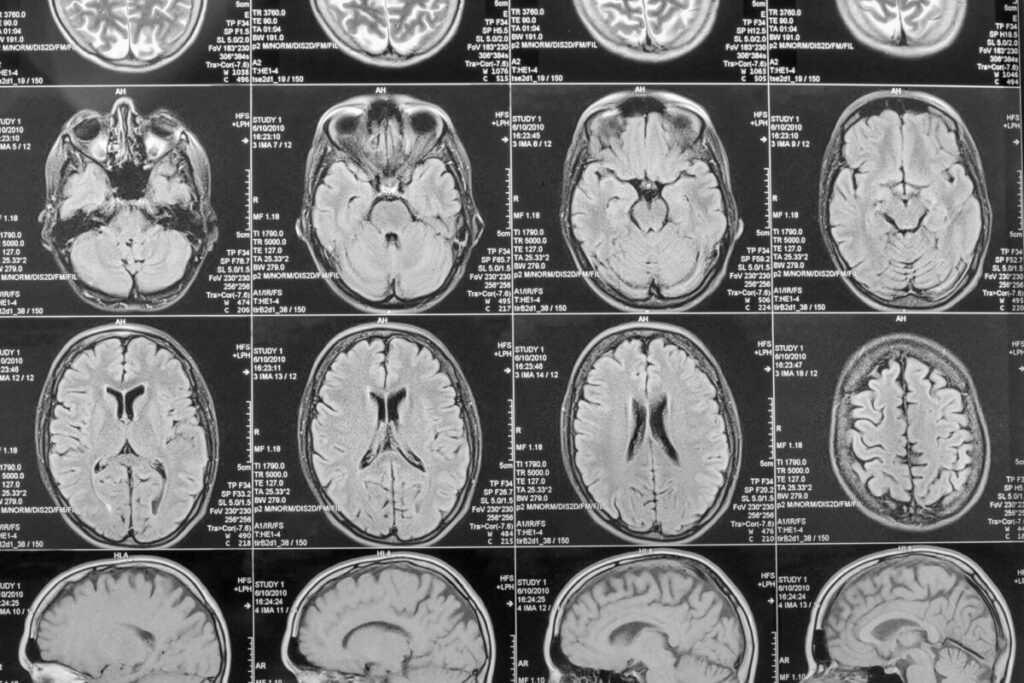

9.脳イメージング革命(1990)

技術:

- MRI

- PET

- fMRI

転換点:精神疾患を脳回路として理解。